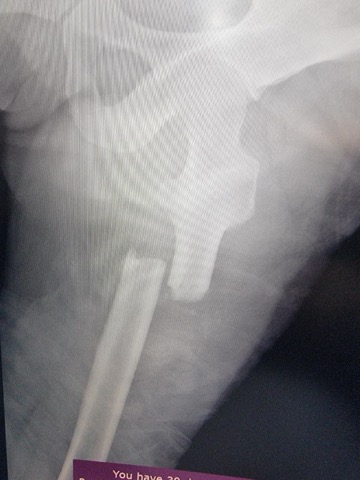

MRI, X-Ray 가지고 있는 사진 첨부했습니다.

무릎 골절, 견갑골 골절, 무릎인대 파열, 대퇴골의 골절, 경골 골절, 흉추 골절, 다발의 타박상, 다발의 찰과상, 뇌진탕